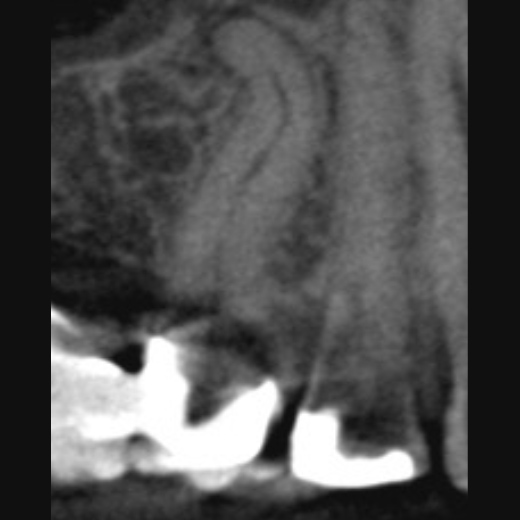

Fallbeispiel: Extraorale Wurzelspitzenresektion (WSR)

Perforationen bei einer Wurzelkanalbehandlung: Ist der Zahn noch zu retten?

Die Wurzelkanalbehandlung ist eine Therapiemöglichkeit, die höchstes Feingefühl erfordert und nicht immer läuft alles reibungslos. So kann es zu sogenannten iatrogenen Perforationen kommen: Das sind unbeabsichtigte Durchlöcherungen des Zahns, die zu unnatürlichen Verbindungen zwischen dem Wurzelkanalsystem und umliegenden Strukturen der Mundhöhle führen. Dadurch können Bakterien und Speichel in den Zahn eindringen, wodurch die Erfolgschancen der Behandlung verringert werden. Dies kann dazu führen, dass der Zahn gezogen werden muss.

Es gibt mehrere Möglichkeiten, Perforationen zu diagnostizieren:

So können z. B. 3D-Röntgenaufnahmen angefertigt und/oder mittels eines sog. Apex-Locators elektronische Kanallängenmessungen durchgeführt werden. Des Weiteren kann der Zahn mithilfe eines Dentalmikroskops inspiziert werden.

Bei der Perforation handelt es sich um die zweithäufigste Komplikation bei der Wurzelkanalbehandlung, doch in vielen Fällen stellt sie kein unlösbares Problem dar. Eine mögliche Abdeckung ist dabei stark von der Größe, Form und Lage der Perforation abhängig. Dabei gilt: Je kleiner und punktförmiger die Läsion, desto besser sind die Chancen, sie erfolgreich abzudichten. Zudem gibt es eine kritische Zone, in der Perforationen die schlechteste Prognose haben. Diese liegt im Bereich zwischen der Zahnfleischoberfläche und dem Beginn des Kieferknochens. Allerdings können eine kieferorthopädische Extrusion des Zahns oder eine chirurgische Kronenverlängerung zu einer erfolgreichen Behandlung dieser ungünstig liegenden Perforationen führen. Auch die Eigenschaften des Wurzelkanals selbst sowie der Zeitpunkt des Auftretens ist von Bedeutung.

Der wichtigste Garant für den Erfolg der Wurzelkanalbehandlung ist natürlich das Vermeiden von Perforationen. Kommt es dennoch dazu, dann gilt es schnell zu handeln: Die Perforation sollte schnellstmöglich mit einem geeigneten Füllmaterial wie MTA verschlossen werden. MTA (Mineral Trioxid Aggregat) zeichnet sich durch eine hohe Biokompatibilität und Dichtigkeit aus.